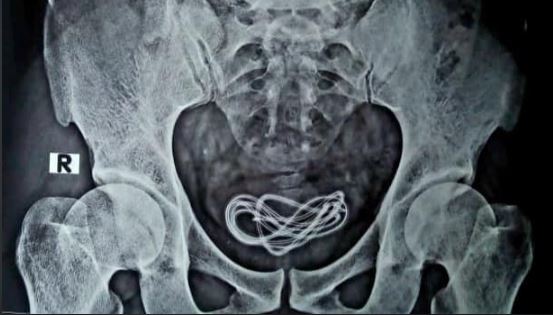

Akhirnya dilakukan pemindaian X-Ray untuk melihat detailnya.

Hasilnya ditemukan benda seperti kabel di dalam perut pasien.

Posisi kabel tersebut ternyata berada di kandung kemih.

Lebih mengejutkan lagi setelah diangkat bukan earphone seperti penuturan pasien.

Tapi yang didapat adalah sebuah kabel pengisian baterai ponsel.

Kabel tersebut dikeluarkan melalui uretra penis.